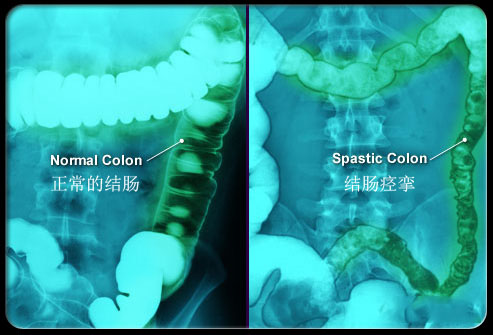

簡單來說腸道激動(dòng)就是腸道蠕動(dòng)過快或者發(fā)生痙攣,對應(yīng)最常見兩大癥狀腹痛和腹瀉:如下所示,腸道蠕動(dòng)過快導(dǎo)致腹瀉、痙攣導(dǎo)致疼痛。